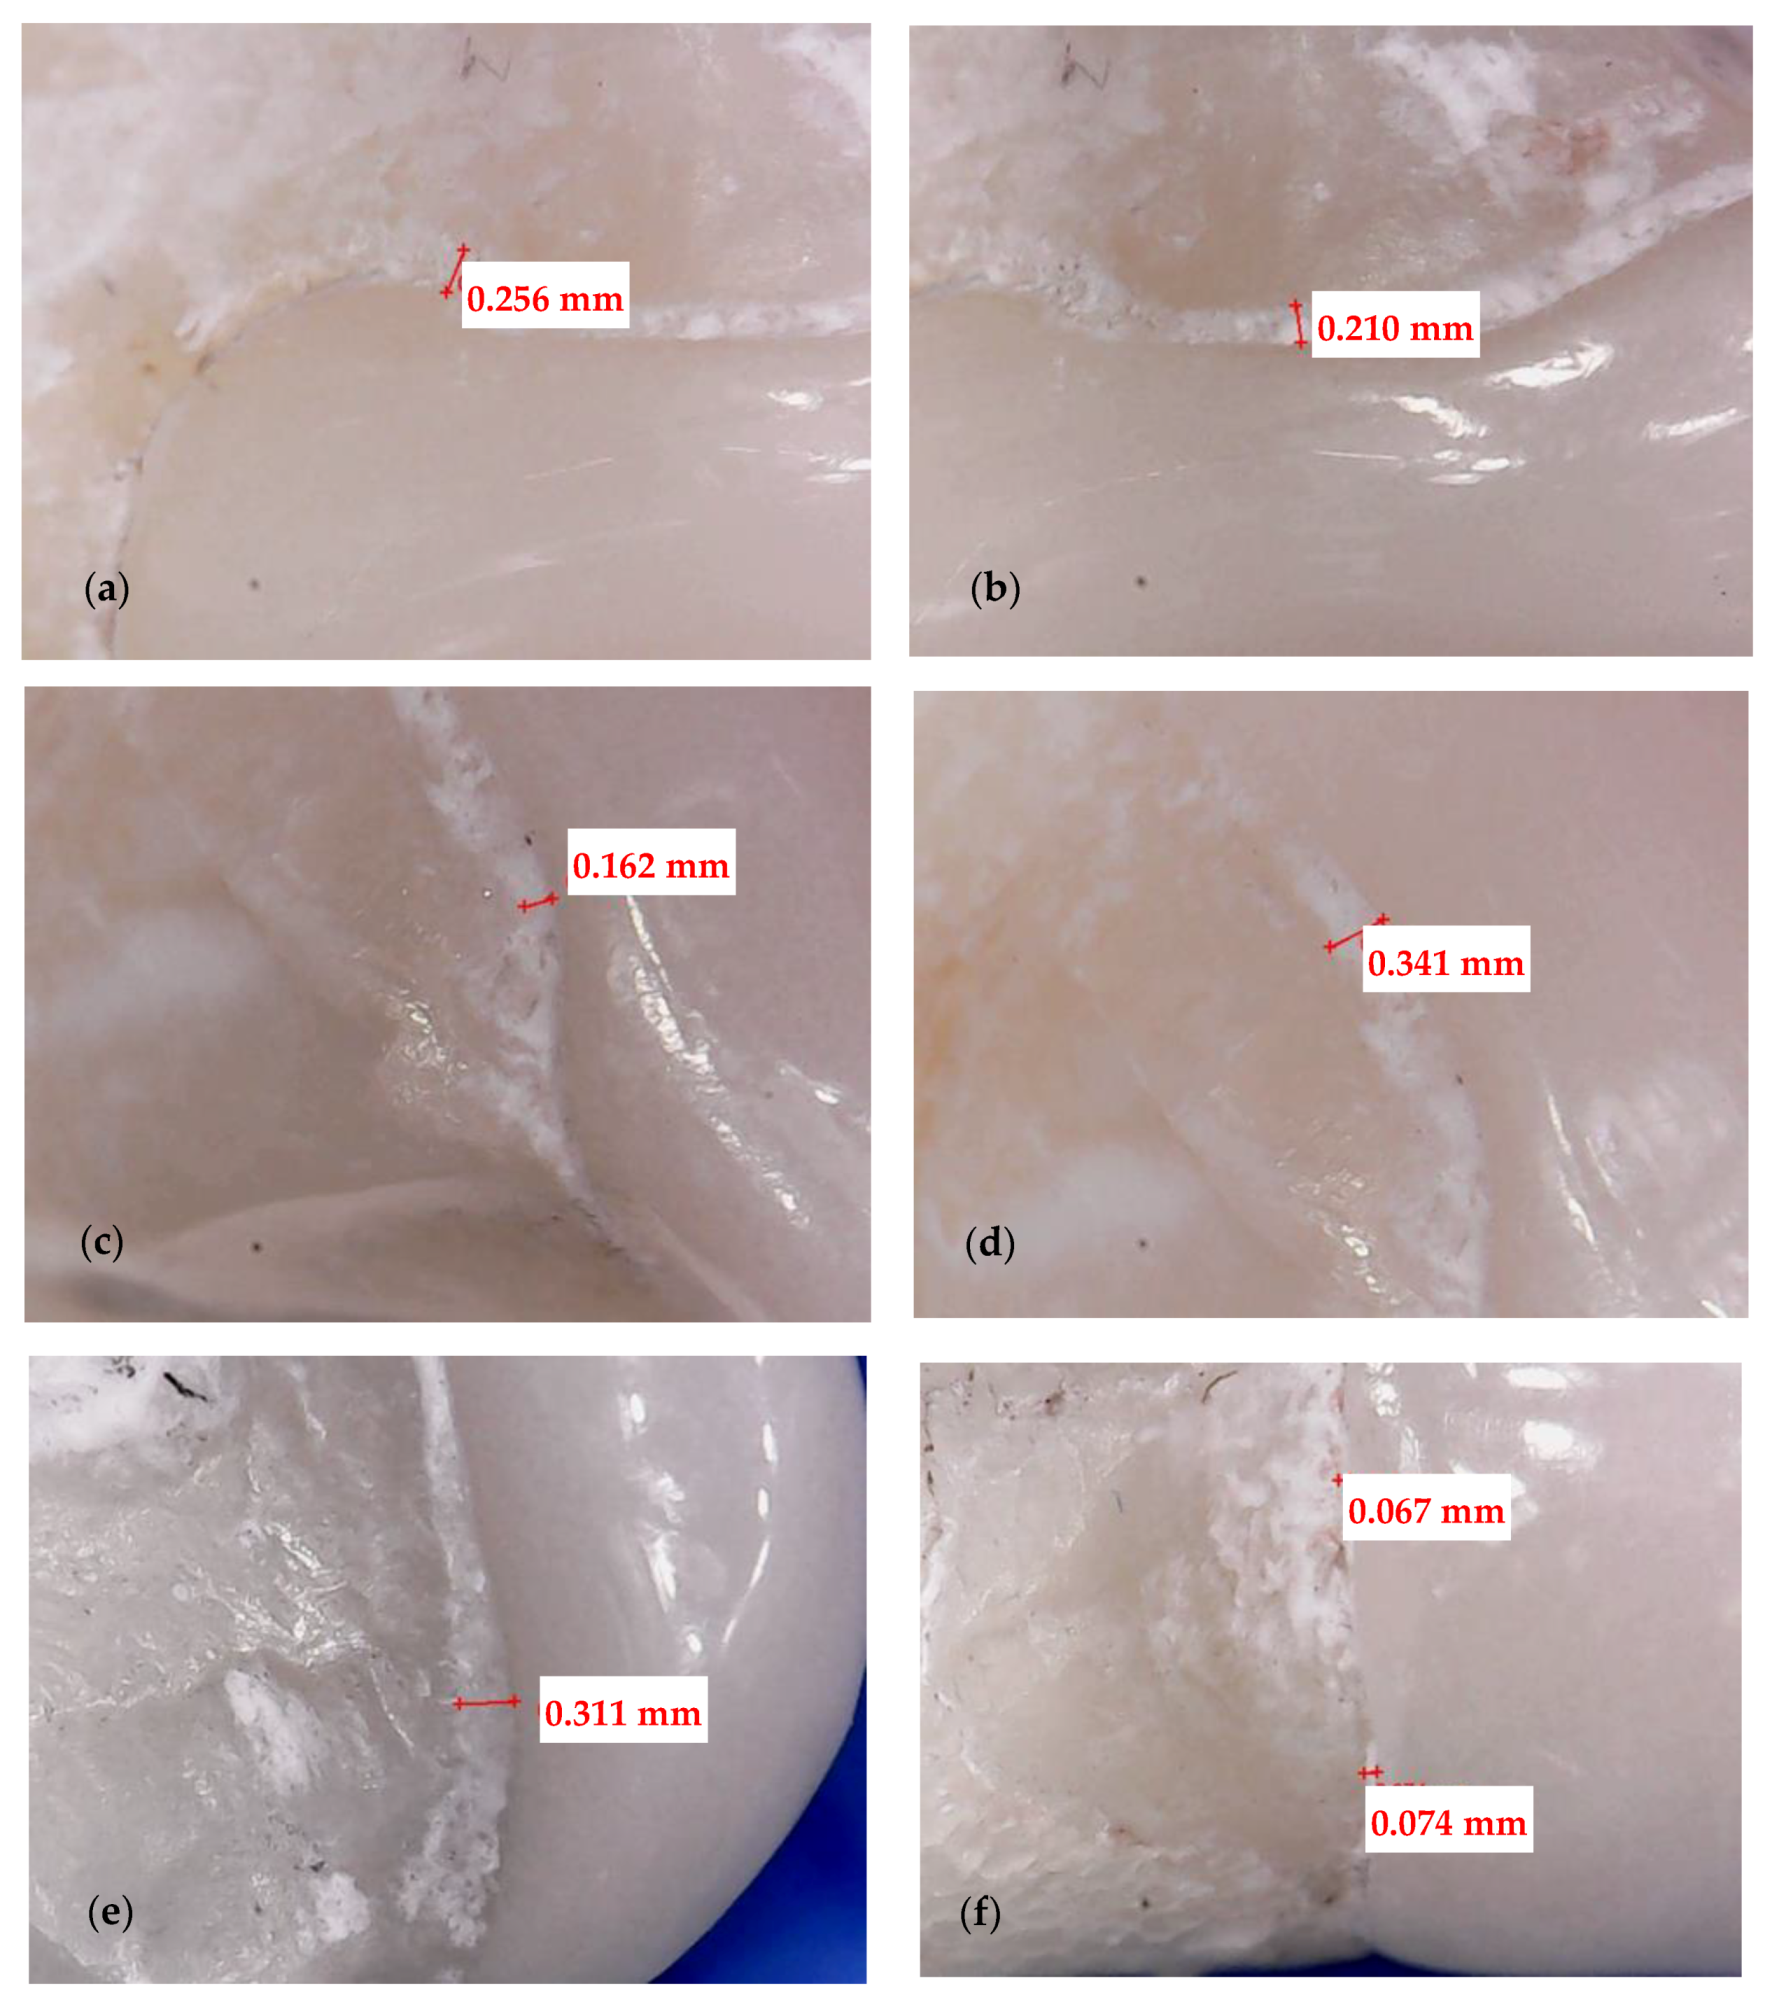

2.3. Optical Microscopy

3.1. Optical Microscopy

- Crenelated (CR) ceramic dental veneers, with their marginal sinusoidal contour, displayed a higher marginal adaptation (60 μm) than the conventional (CO) (with linear margins) veneers (230 μm).

- Micro-CT proved to be reliable and precise to evaluate the internal adaptation of the restorations, as well as the porosities localized in the luting cement. It has the advantage of providing 3D information on the entire volume of dental cement (i.e., the interface between dental support and veneers). The more common and accessible tool, optical microscopy, provided valuable data regarding the marginal adaptation, with a good agreement with the micro-CT results, but cannot evaluate internal adaptation.